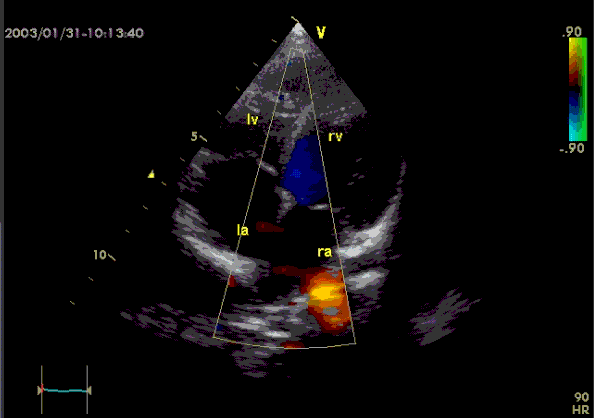

(Als je op het plaatje klikt, gaat het kloppen)

We zitten in een het Lucas ziekenhuis, wachtend op het echofilmpje van haar hart – onderzoek naar mogelijk hartfalen. Dat is dat je hart het zuurstofrijke bloed niet meer goed rondpompt, zodat je koude voeten, koude handen, een koude neus krijgt. En in een gesprek snel buiten adem raakt. We wachten op onze beurt. Mijn moeder doet, om de tijd te verdrijven, het Loerende Mannetje na. Ze doet het goed.

We zijn in het Lucas. Het is het tijd voor de echo van het hart. Dat klopt. Regelmatig. Gestaag. Al 91 jaar. Still going strong.